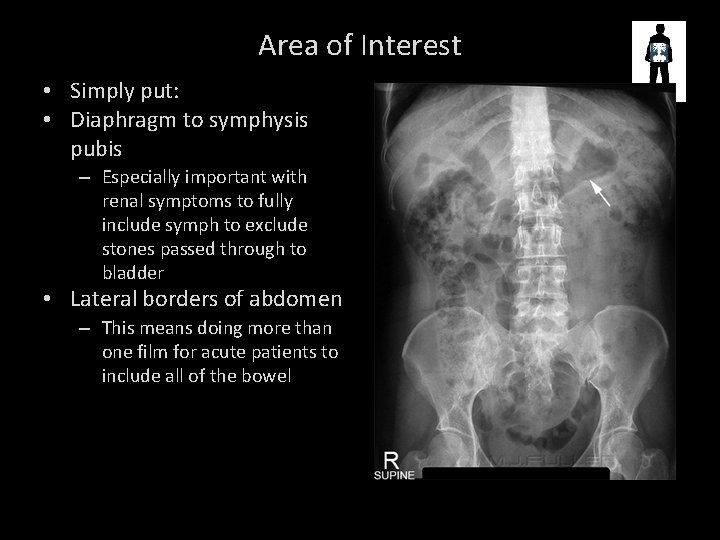

Area of Interest • Simply put: • Diaphragm to symphysis pubis – Especially important with renal symptoms to fully include symph to exclude stones passed through to bladder • Lateral borders of abdomen – This means doing more than one film for acute patients to include all of the bowel